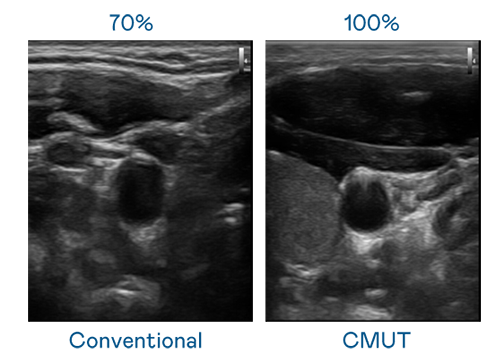

CMUT 技术是一种用电容式微机电元件来产生超音波讯号的技术。与传统 PZT 压电式技术相比,CMUT 频宽增加 30%,更宽频的超音波讯号让影像解析度大幅提升,是实现高影像品质医疗超音波扫描、促进精准医疗发展的关键技术。

大频宽带来超清晰影像

超音波影像的解析度高低,首先取决于探头能发出的讯号频宽。EMC易倍 CMUT 可提供高清晰的超音波讯号,提供高频宽、高灵敏度、影像纹理细节更高的超音波影像,协助医护人员缩短影像判读时间及利用精准的医疗影像进行诊断。